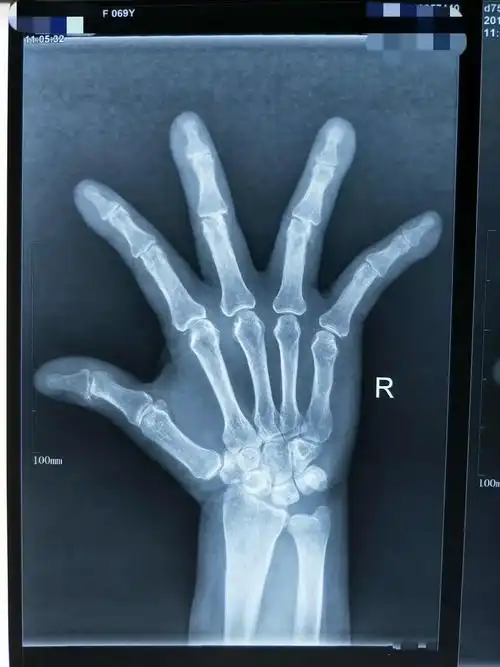

他的双手手指关节反复肿痛,畸形3年多.

手指关节疼痛变形一定是类风湿吗?

老嗲嗲手指关节变形严重检查又没啥问题这是咋回事呢